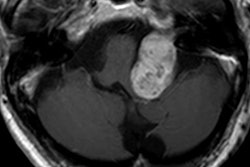

VIENNA - Gadolinium phobia remains a very real danger in Europe, but practical measures can help to reduce the risk, according to Dr. Johannes Heverhagen, PhD, professor and head of radiology at the University Hospital of Bern in Switzerland. In advance of Friday's ECR special focus session on the safety of gadolinium contrast agents for MRI, he also provides an update on the European Medicines Agency's investigation, the results of which are expected soon.